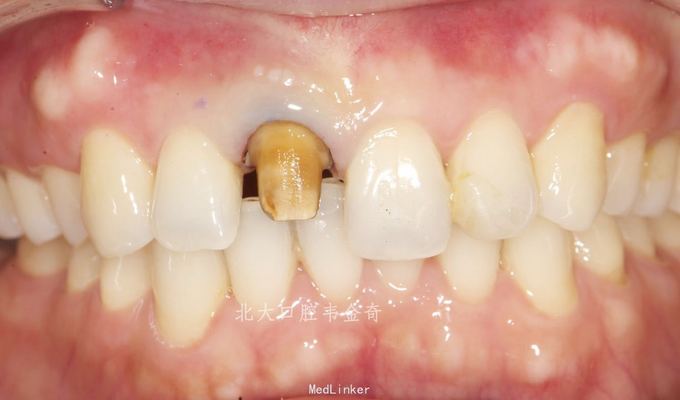

诊断:11牙体缺损,牙冠变色。 处理:建议桩核冠修复。常规操作完成纤维桩树脂核,以及铸瓷冠修复。